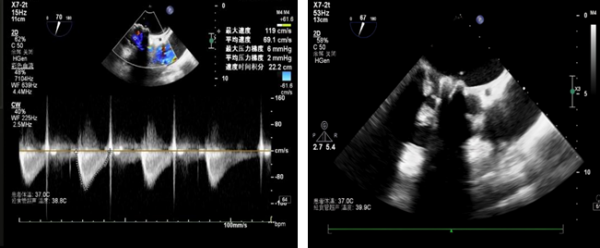

术后心脏彩超所示:二尖瓣无返流

术后即刻造影与超声检查结果令人振奋:新植入的人工瓣位置合适、形态完整,开放功能正常,未见瓣中和瓣周反流,手术取得圆满成功!在医护团队的精心照料下,刘英芳术后恢复顺利,胸闷、气喘等不适症状明显缓解,身体状态一天天好转,家人悬着的心也终于放了下来。